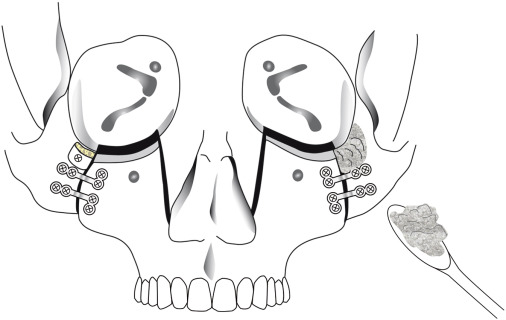

2. QUADANGULAR LEFORT + BSSO + GENIOPLASTY

quadangular lefort less risky than MLF3/LF2)

2. QUADANGULAR LEFORT + BSSO + GENIOPLASTY

quadangular lefort